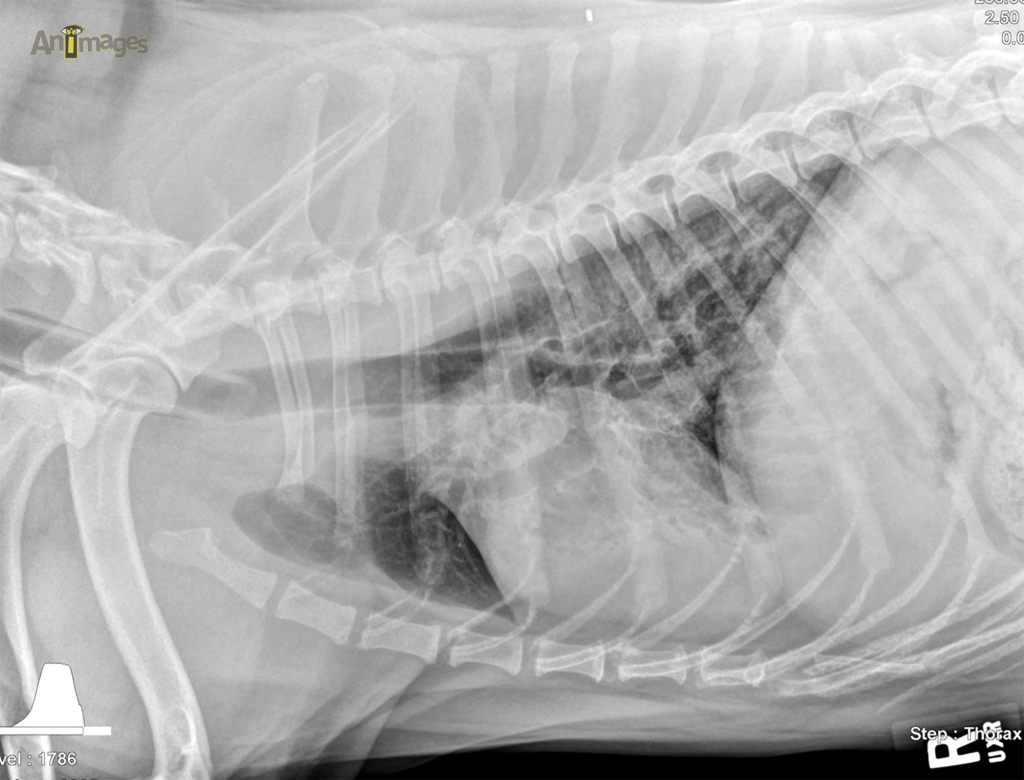

lat D

Latérale droite